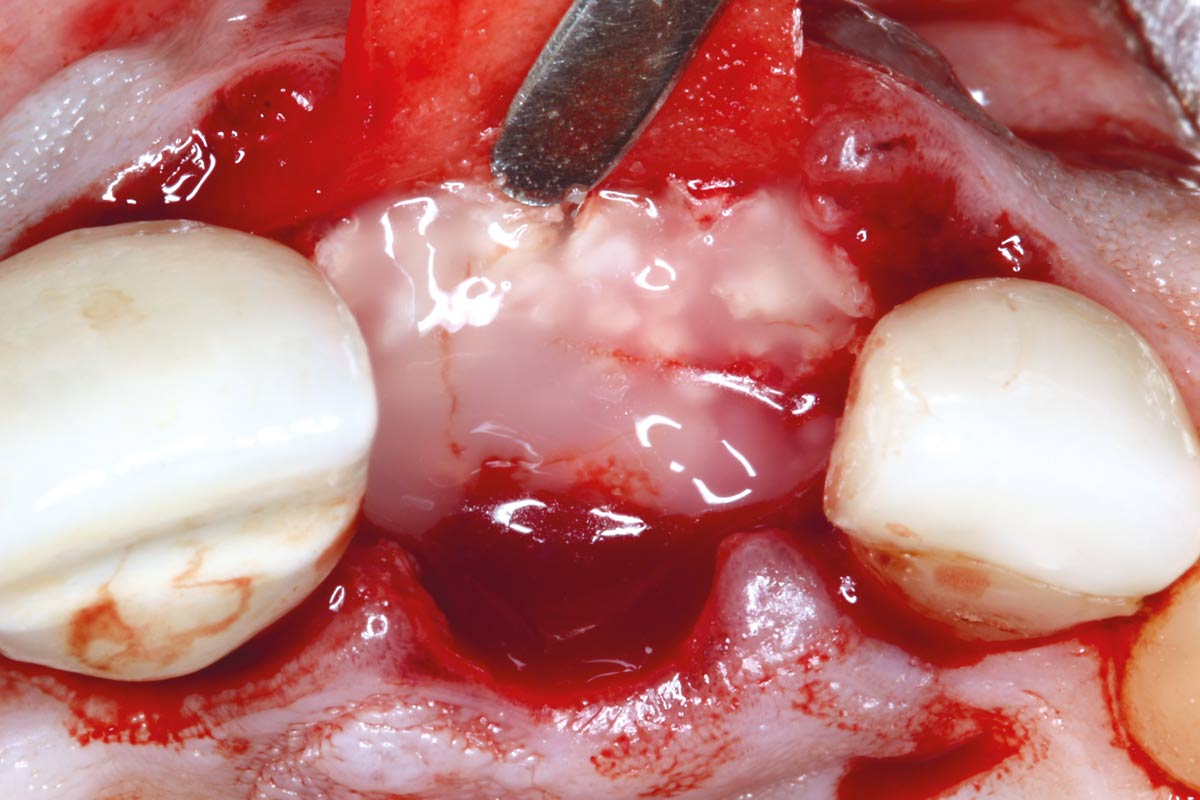

05/10 - Socket augmented with maxgraft® granules coated with Straumann® Emdogain®

Socket augmentation using mucoderm®, maxgraft® and Straumann® Emdogain® - Dr. A. Puišys